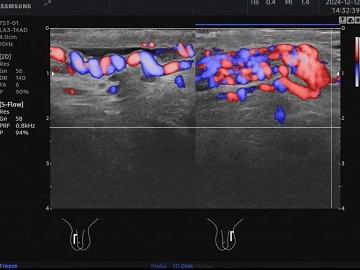

精索静脉曲张

✅准确筛查,锁定隐蔽男性问题:医院拥有专业检测设备,针对精索静脉曲张、隐睾、鞘膜积液、精索附睾小结节等问题,可实现准确定位、分级诊断,甚至早期小病变也能迅速检测,为年轻人提前消除体检“雷区”;